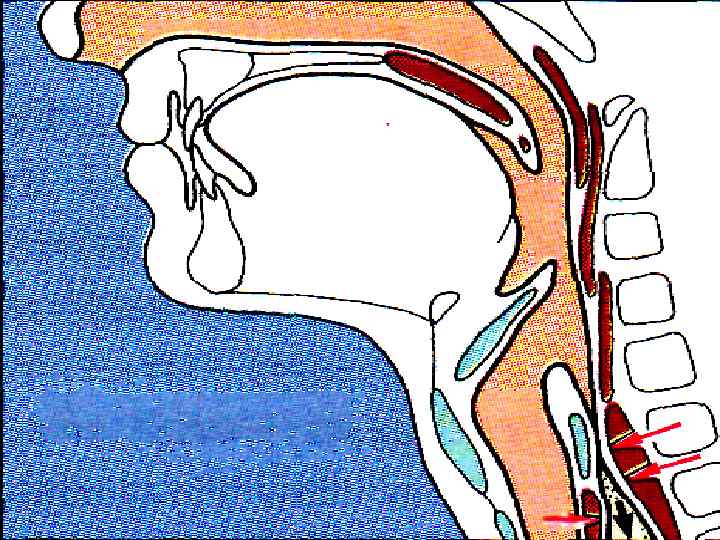

ФАЗЫ ГЛОТАНИЯ РОТОВАЯ (ПРОИЗВОЛЬНАЯ) ГЛОТОЧНАЯ ПИЩЕВОДНАЯ

ФАЗЫ ГЛОТАНИЯ РОТОВАЯ (ПРОИЗВОЛЬНАЯ) ГЛОТОЧНАЯ ПИЩЕВОДНАЯ

ГЛОТОЧНАЯ ФАЗА

ГЛОТОЧНАЯ ФАЗА

1. МЯГКОЕ НЕБО ЗАКРЫВАЕТ ХОАНЫ 2. НЕБНО-ГЛОТОЧНЫЕ СКЛАДКИ – САГИТТАЛЬНУЮ ЩЕЛЬ 3. ГОЛОСОВАЯ ЩЕЛЬ СМЫКАЕТСЯ, ГОРТАНЬ ПОДТЯГИВАЕТСЯ ВВЕРХ → НАДГОРТАННИК – КЗАДИ

1. МЯГКОЕ НЕБО ЗАКРЫВАЕТ ХОАНЫ 2. НЕБНО-ГЛОТОЧНЫЕ СКЛАДКИ – САГИТТАЛЬНУЮ ЩЕЛЬ 3. ГОЛОСОВАЯ ЩЕЛЬ СМЫКАЕТСЯ, ГОРТАНЬ ПОДТЯГИВАЕТСЯ ВВЕРХ → НАДГОРТАННИК – КЗАДИ

4. ПИЩЕВОД – ВВЕРХ, ВХОД РАСШИРЯЕТСЯ 5. ВЕРХНИЙ ПИЩЕВОДНЫЙ СФИНКТЕР РАСКРЫВАЕТСЯ 6. ГЛОТКА СОКРАЩАЕТСЯ, ПРОТАЛКИВАЯ ПИЩУ t=2 c

4. ПИЩЕВОД – ВВЕРХ, ВХОД РАСШИРЯЕТСЯ 5. ВЕРХНИЙ ПИЩЕВОДНЫЙ СФИНКТЕР РАСКРЫВАЕТСЯ 6. ГЛОТКА СОКРАЩАЕТСЯ, ПРОТАЛКИВАЯ ПИЩУ t=2 c